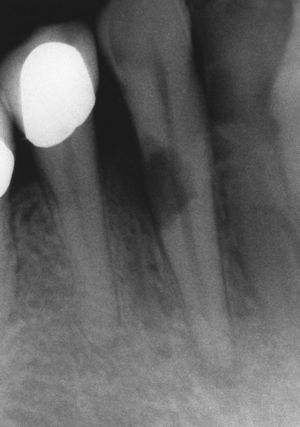

Características radiográficasDesde el punto de vista radiográfico, las reabsorciones externas (fig. 6) se caracterizan por los siguientes signos:

- •

Luz del conducto radicular no dilatada.

Imagen radiolúcida en la zona radicular de límites irregulares.

Localización asimétrica.

La localización cambia con la proyección radiológica excéntrica.

Desaparición localizada del espacio periodontal.